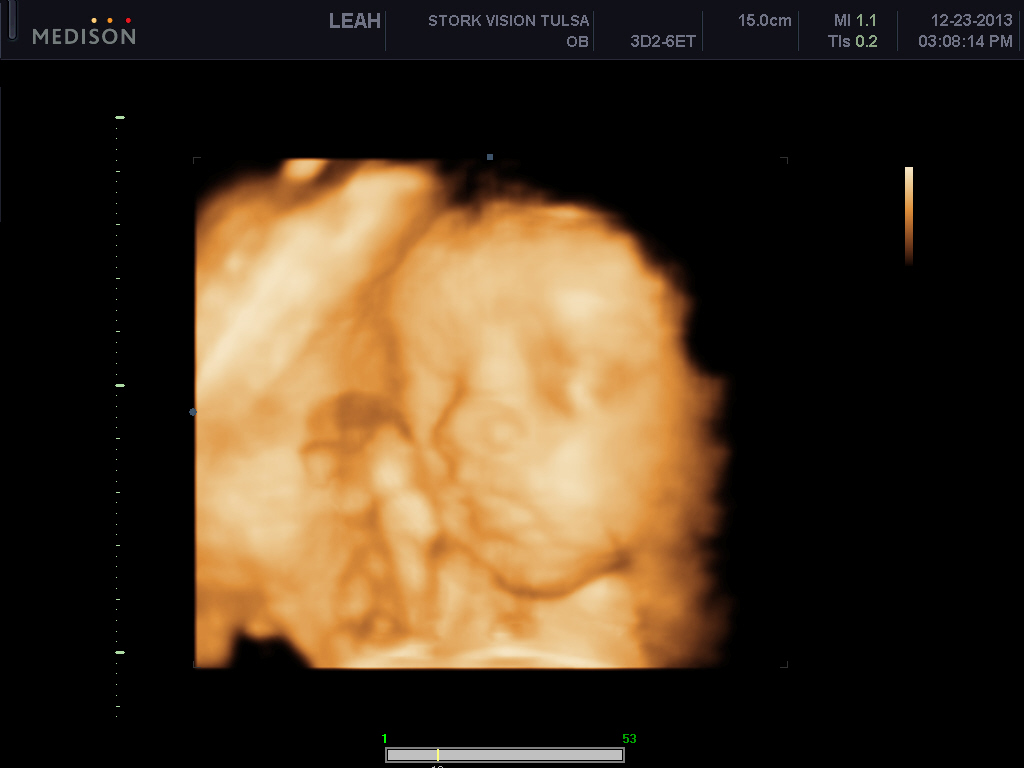

He's freaking adorable! These are my favs out of about 70 pictures..

Look at those cheeks!